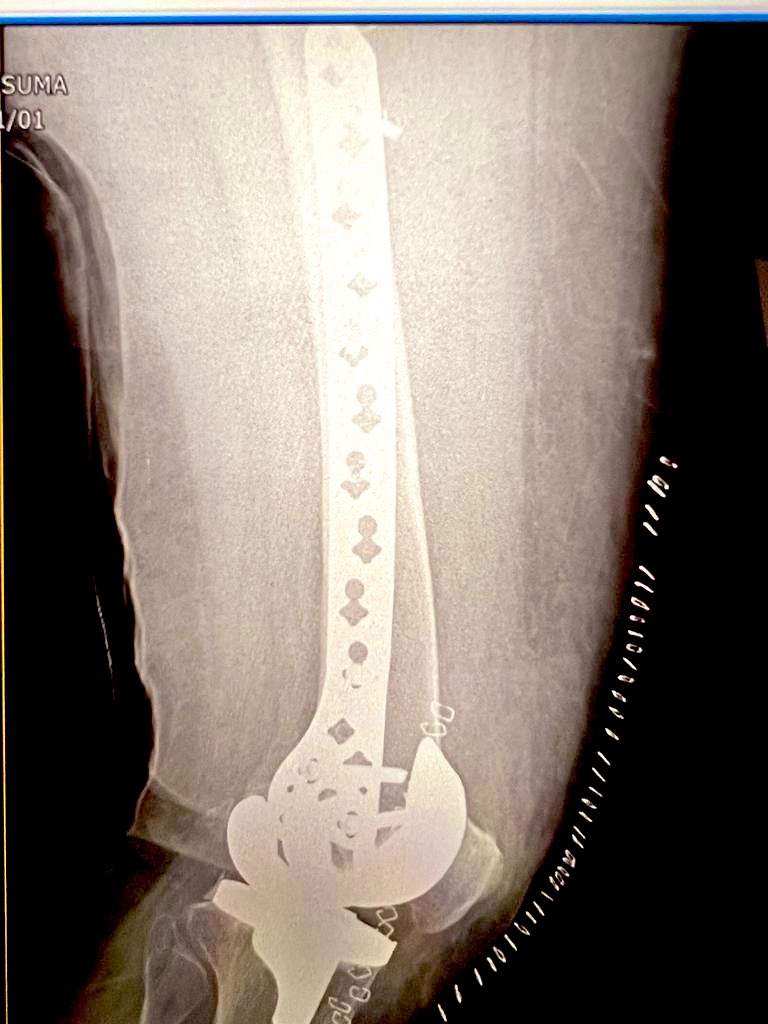

They finally decided to use β€œless invasive variable locking plate” from Synthes for her.

The end result was marvellous, with small 3 inch incision & few punctures to pass screws on proximal end of implant

In fifty days this was the status. We allowed partial weight bearing but told her not to move around a lot.

Exactly 80 days after her fracture & fixation we took another X Ray.

It showed good recovery, increasing bone density & some micro trabecular patterns.